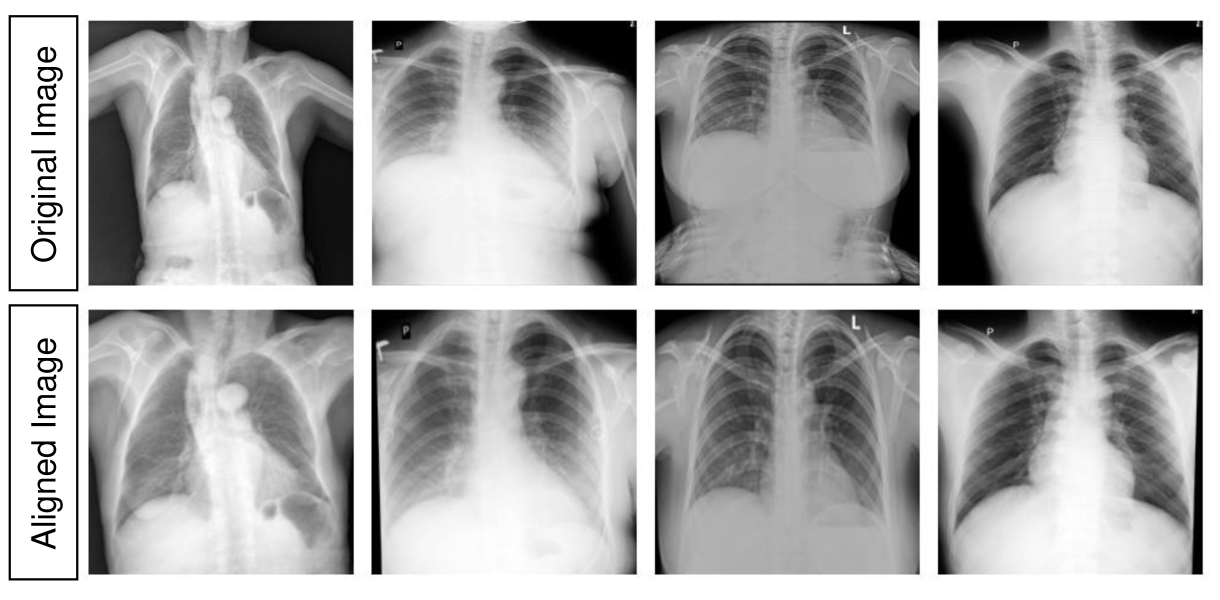

The chest X-ray images from a dataset generally have diverse variations, such as rotations, shifts, and different scales, making it challenging for the deep-learning models to localize the lesion areas. To address this problem, we utilize the alignment module [41] to perform spatial alignment on all the images as well as on the bounding box images for generating abnormality masks. Given the input image , the alignment module transforms to . The canonical chest X-ray image, known as the target image , is generated by randomly selecting two thousand normal chest X-ray images and averaging them to a single image. To provide with an aligned structure, we minimize the feature reconstruction loss [42] between and . The backbone of the alignment module consists of ResNet-18 architecture. The output of the alignment network is the affine transformation parameters. Finally, the affine transformation is applied to the original chest X-ray images to generate aligned chest X-ray images. Fig. 5 shows some examples of original and aligned X-ray images.